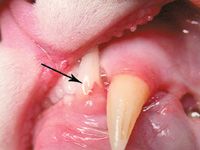

Photo 1: A triangular-shaped defect in the tooth at the gingival margin (arrow) is evident. This generally occurs in Type 1 and longer-standing Type 2 tooth resorption.

Grossly, Type 1 tooth resorption is characterized by gingivitis and periodontitis generally initiated at the junction between the cementum and the enamel. The origin is thought to be inflammatory. Cavitation defects are seen in the crown, with inflamed gingival tissue often covering the defect (Photo 1). Radiographically, these teeth have variations in density in the crown or root. A distinct periodontal ligament space is generally appreciated (Photo 2). Type 1 and Type 2 tooth resorption may be observed concurrently in individual roots of a single tooth (Photo 3). Therefore, diagnostic evaluation of each root is important to determine how each should be approached therapeutically.